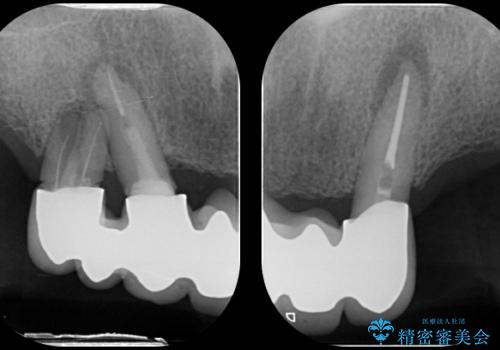

- 前歯がグラグラして噛めない、現在使っている入れ歯も全然合わない。

今後しっかりと噛んで食事できるような治療を希望され来院されました。

インプラント支台のマグネットを用いることで安定してしっかりと噛めるような総義歯治療を計画します。